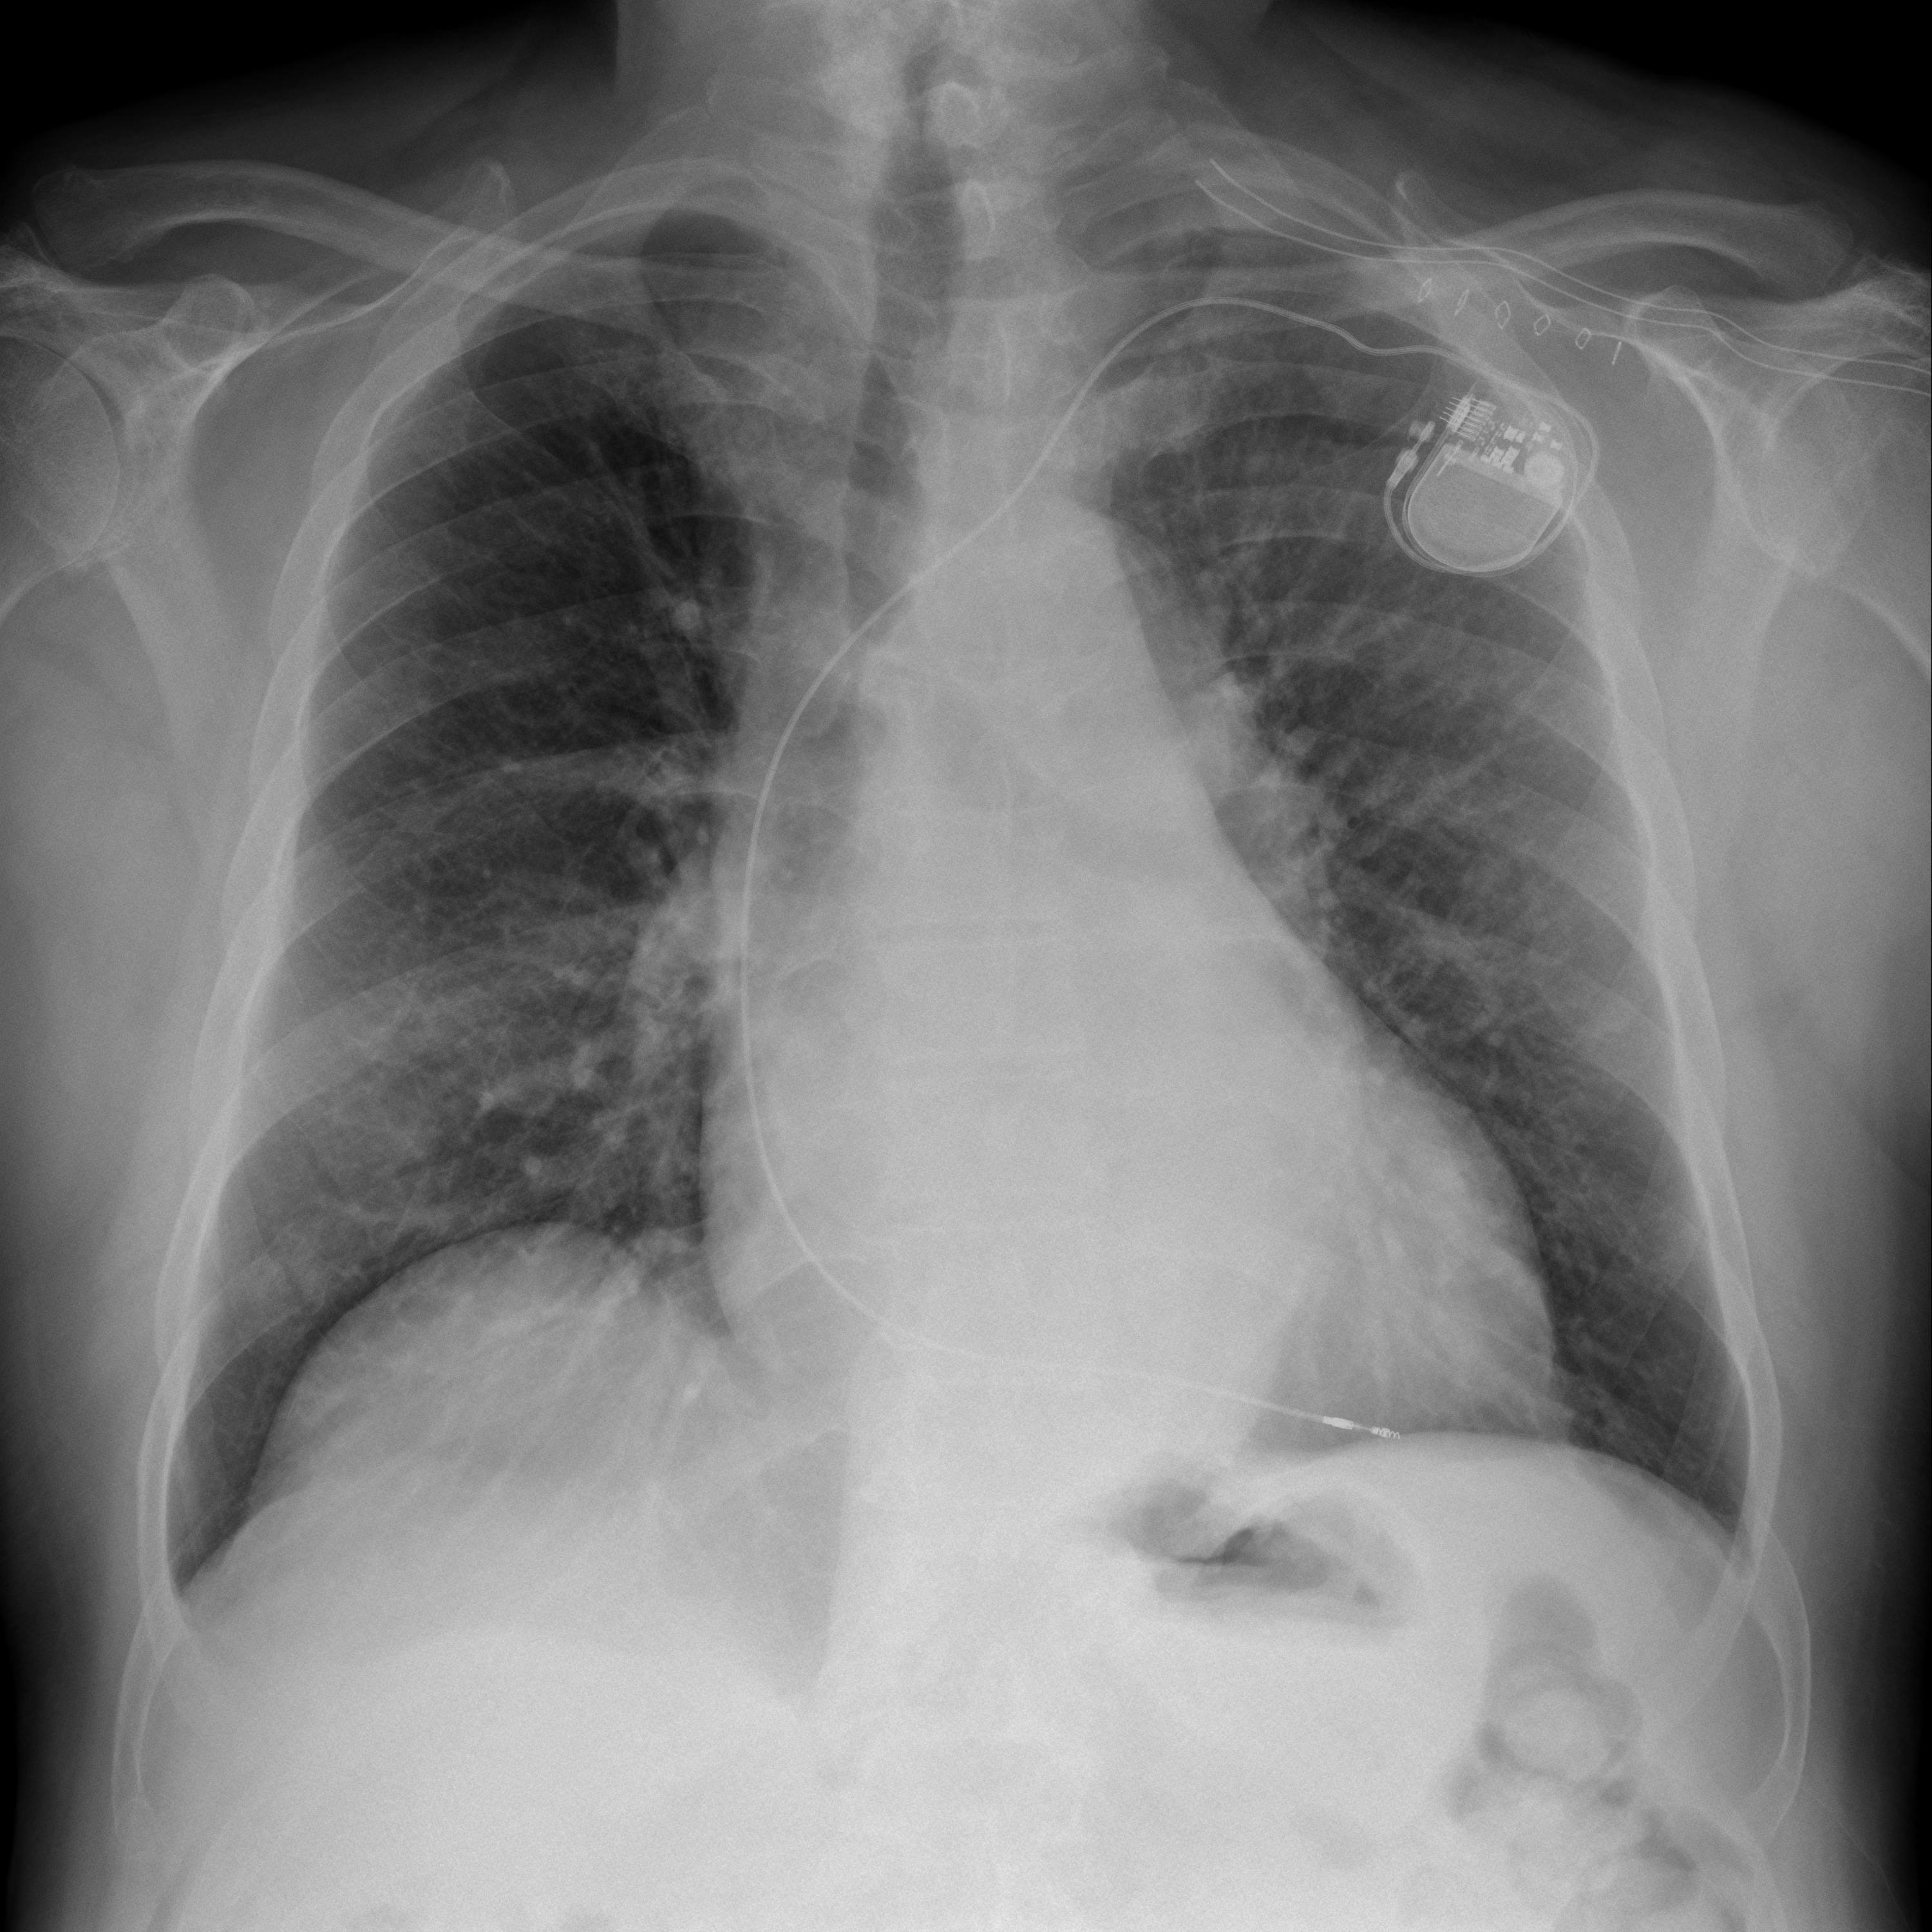

의료 영상 분석기

의료 영상 분석기(MIA) 프로젝트는 PyTorch 및 OpenCV를 활용하여 흉부 방사선 촬영(CR) 영상을 분석하여 의료 진단 및 치료 계획을 향상시키는 데 중점